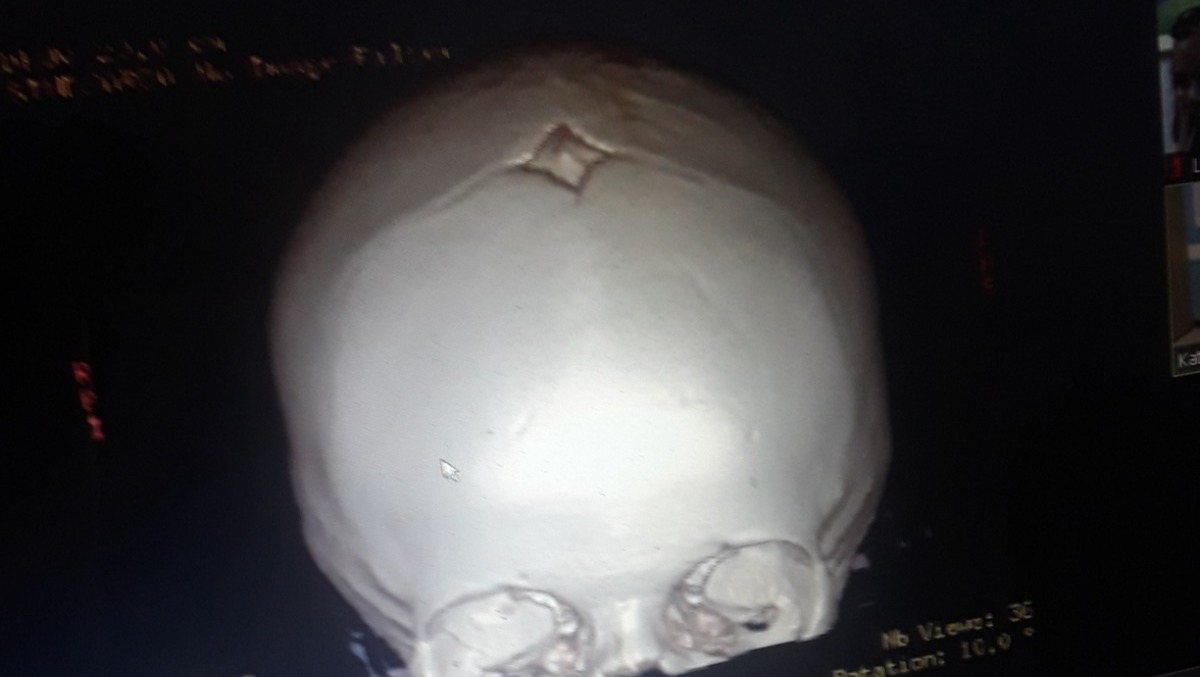

Our 15 month old Zoey LeeAnn was diagnosed with bicoronal craniosynostosis, and a simple doctor's appointment became a life changing event in the blink of an eye. After talking with the neurosurgeon and plastic surgeon we understand surgery is necessary. We find comfort in knowing God is with us  and that he gave us the very best team available Stanford has the very best facilities and doctors around. There are so many obstacles ahead that we are not prepared for. Knowing we are in the best of hands makes it a little bit easier . Zoey will be having surgery on December 17th at Lucile Packard childrens hospital at Stanford in Palo Altos California. Zoey will have pre-op appointments with her neurosurgeon plastic surgeon and the anesthesiologist on December 14th meaning we will need to fly out to California from Reno Nevada on the 12th or 13th of December. Her surgery is scheduled for the 17th and with the recovery time we believe we will be home around December 28th . We know the holidays are coming up and it's been a hard year for everybody but we are humbly asking for monetary donations to help with the costs of out of state travel, stay, food, and any unexpected cost during Zoeys surgery. Please if possible please help ease the financial stress, and allow us to focus on Zoeys surgery and recovery. And please please pray for Zoey LeeAnn she is our sweet sunflowers  brightening the day of everyone she meets. We love you Zoey LeeAnn.